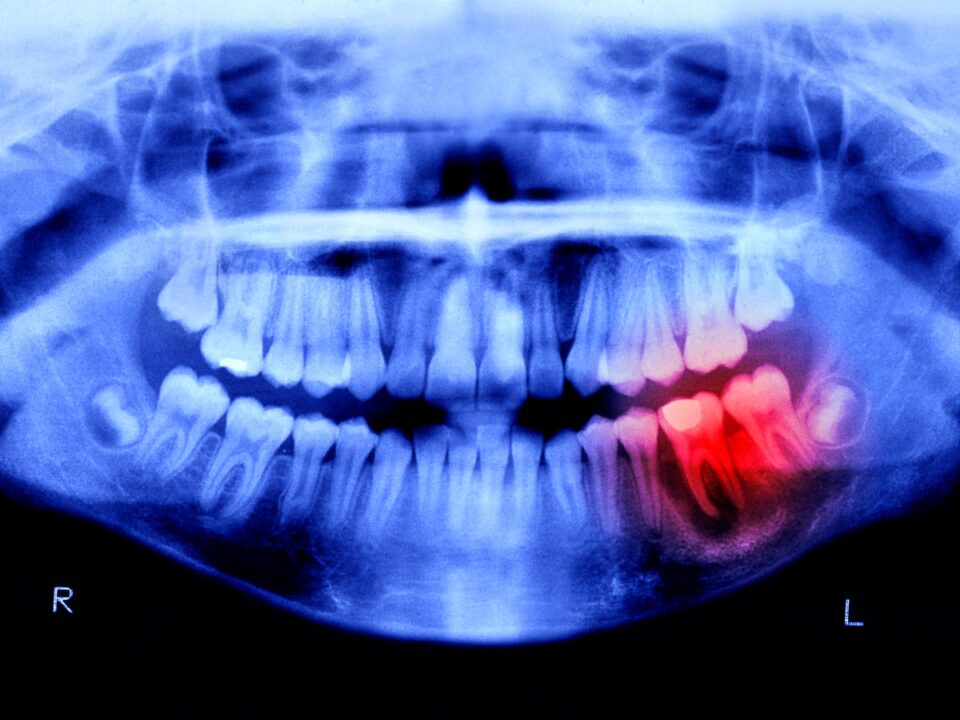

دندانها اگرچه از سختترین مواد بدن ساخته شدهاند و مینای دندان آنها را بهخوبی محافظت میکند، اما برخلاف استخوانها توانایی ترمیم طبیعی ندارند. محققان ژاپنی سالهاست در تلاشاند این محدودیت زیستی را پشت سر بگذارند. نتیجه این تلاشها، تمرکز بر آنتیبادی ویژهای به نام USAG-1 بوده که نقش مهارکنندهای در رشد دندان دارد.

در سال ۲۰۲۱، دانشمندان دانشگاه کیوتو موفق شدند یک آنتیبادی مونوکلونال شناسایی کنند که تعامل میان USAG-1 و پروتئینهای مورفوژنتیک استخوان (BMP) را مختل میکند؛ پروتئینهایی که در رشد استخوان و دندان نقش کلیدی دارند. سرکوب این ژن در آزمایشهای حیوانی، منجر به رشد دندانهای جدید در موشها و خرگوشهای صحرایی شد؛ حیواناتی که الگوی دندانی آنها شباهت زیادی به انسان دارد.

اکنون این پژوهش وارد مرحله آزمایش انسانی شده است. مطالعهای ۱۱ ماهه روی ۳۰ مرد بین ۳۰ تا ۶۴ سال که حداقل یک دندان از دست دادهاند، در حال انجام است. دارو بهصورت تزریق وریدی استفاده میشود تا ایمنی و اثربخشی آن بررسی شود. نکته امیدوارکننده این است که در مطالعات حیوانی پیشین، هیچ عارضه جانبی جدی گزارش نشده است.